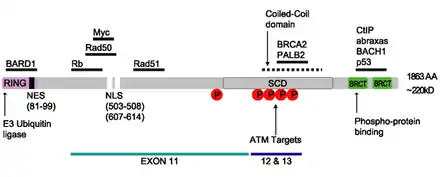

The human BRCA1 protein consists of four major protein domains; the Znf C3HC4- RING domain, the BRCA1 serine domain and two BRCT domains. These domains encode approximately 27% of BRCA1 protein. There are six known isoforms of BRCA1,[28] with isoforms 1 and 2 comprising 1863 amino acids each.

Zinc ring finger domain

The RING motif, a Zn finger found in eukaryotic peptides, is 40–60 amino acids long and consists of eight conserved metal-binding residues, two quartets of cysteine or histidine residues that coordinate two zinc atoms.[30] This motif contains a short anti-parallel beta-sheet, two zinc-binding loops and a central alpha helix in a small domain. This RING domain interacts with associated proteins, including BARD1, which also contains a RING motif, to form a heterodimer. The BRCA1 RING motif is flanked by alpha helices formed by residues 8–22 and 81–96 of the BRCA1 protein. It interacts with a homologous region in BARD1 also consisting of a RING finger flanked by two alpha-helices formed from residues 36–48 and 101–116. These four helices combine to form a heterodimerization interface and stabilize the BRCA1-BARD1 heterodimer complex. Additional stabilization is achieved by interactions between adjacent residues in the flanking region and hydrophobic interactions. The BARD1/BRCA1 interaction is disrupted by tumorigenic amino acid substitutions in BRCA1, implying that the formation of a stable complex between these proteins may be an essential aspect of BRCA1 tumor suppression.[30]

Serine cluster domain

BRCA1 serine cluster domain (SCD) spans amino acids 1280–1524. A portion of the domain is located in exons 11–13. High rates of mutation occur in exons 11–13. Reported phosphorylation sites of BRCA1 are concentrated in the SCD, where they are phosphorylated by ATM/ATR kinases both in vitro and in vivo. ATM/ATR are kinases activated by DNA damage. Mutation of serine residues may affect localization of BRCA1 to sites of DNA damage and DNA damage response function.[29]

BRCT domains

The dual repeat BRCT domain of the BRCA1 protein is an elongated structure approximately 70 Å long and 30–35 Å wide.[32] The 85–95 amino acid domains in BRCT can be found as single modules or as multiple tandem repeats containing two domains.[33] Both of these possibilities can occur in a single protein in a variety of different conformations.[32] The C-terminal BRCT region of the BRCA1 protein is essential for repair of DNA, transcription regulation and tumor suppressor function.[34] In BRCA1 the dual tandem repeat BRCT domains are arranged in a head-to-tail-fashion in the three-dimensional structure, burying 1600 Å of hydrophobic, solvent-accessible surface area in the interface. These all contribute to the tightly packed knob-in-hole structure that comprises the interface. These homologous domains interact to control cellular responses to DNA damage. A missense mutation at the interface of these two proteins can perturb the cell cycle, resulting a greater risk of developing cancer.